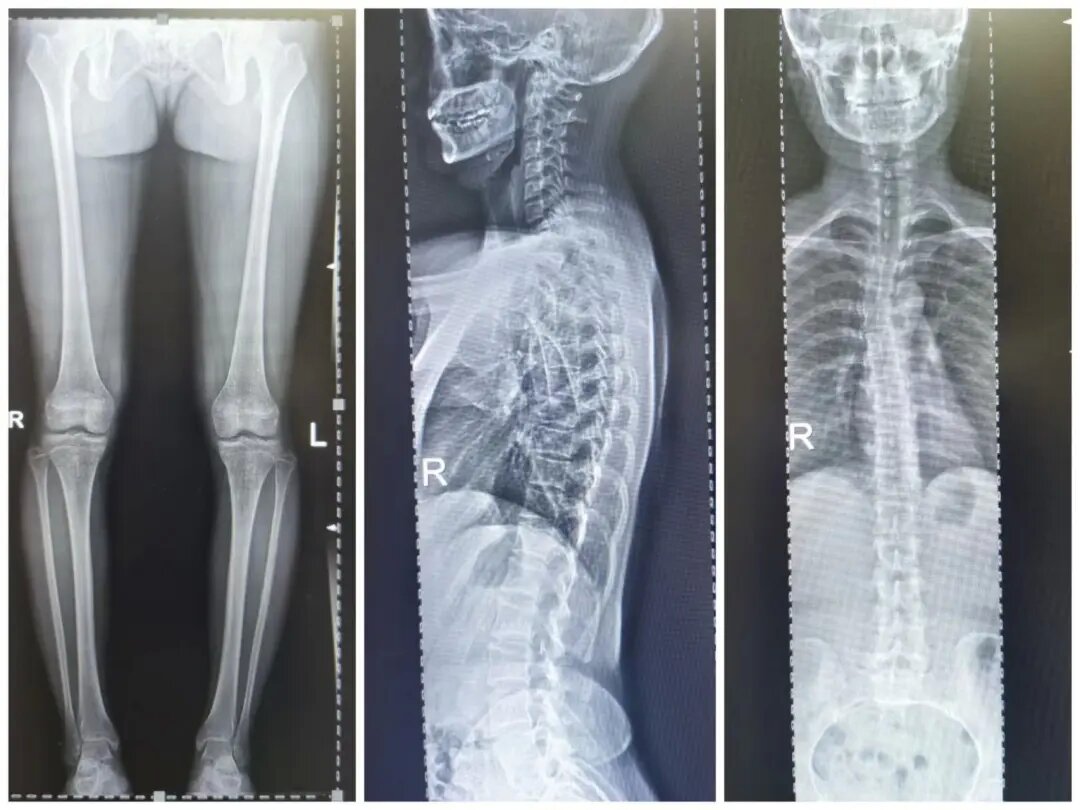

四、脊柱全長攝影及雙下肢全長攝影

對脊柱側彎、髖關節置換、膝關節置換給予全面、直觀的影像資料。